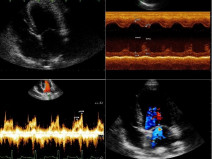

• Les ateliers d'échocardiographie

Ces travaux pratiques, réalisés par manipulation sur les chiens de compagnie appartenant aux participants, s’adressent à des vétérinaires canins désirant se former à l’échographie et disposant d’un échographe dans leur pratique quotidienne, ou souhaitant en acquérir un rapidement.

Du 16 au 17 mai 2018

Saint-Gatien-des-Bois (14130)

Imagerie Médicale

Normandie